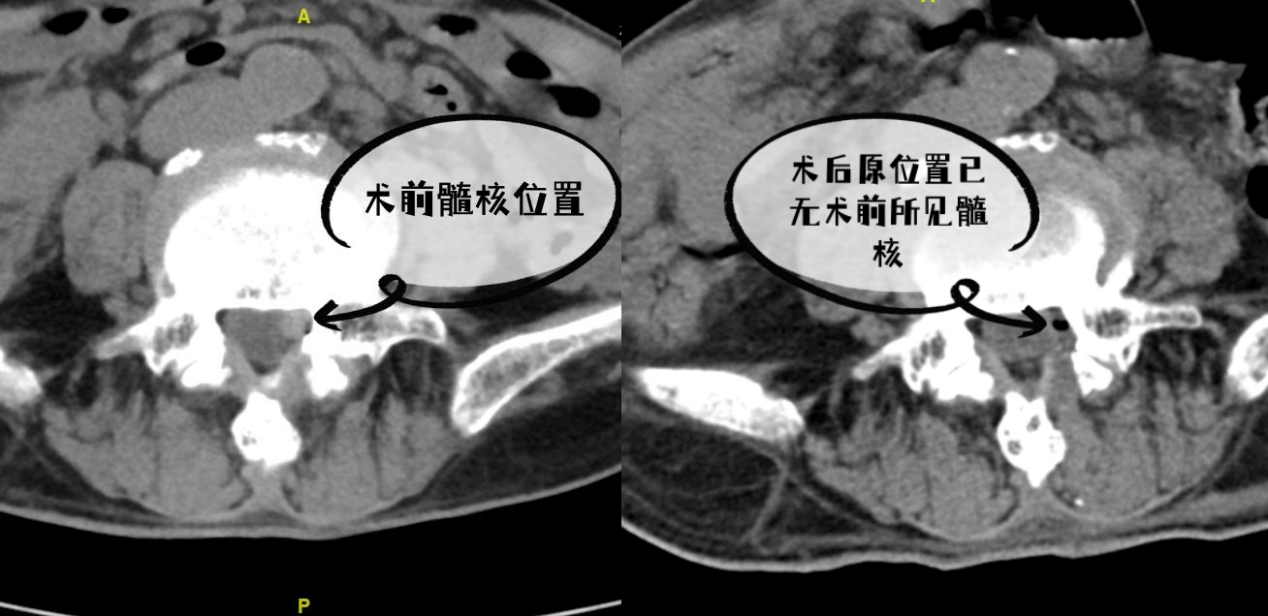

接诊后,脊柱外科主任邵朋带领医疗团队迅速为纪先生进行了详细检查,最终确诊其病因为L4/5椎间盘髓核脱出。考虑到患者年龄较高,传统开放手术风险较大,团队决定采用单边双通道内镜微创技术进行治疗。

单边双通道内镜微创技术是目前脊柱微创手术中的先进术式,仅需两个约1厘米的微小切口,即可在清晰视野下精准处理病变组织。该技术对脊柱周围肌肉、韧带损伤小,术中出血少,能显著缩短术后恢复时间。在邵朋的精细操作下,手术顺利完成。术后第二天,纪先生即可佩戴护具下床活动,左腿疼痛麻木症状基本消失。术后随访显示,纪先生恢复良好,未出现复发迹象。